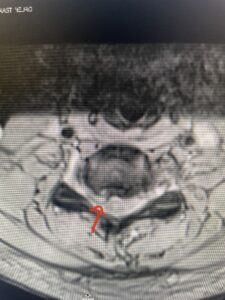

This 36-year-old female who had a long history of neck pain had a history on MRI of a C5-6 bulge. She recently after diving into a pool (not hitting her head on bottom) developed progressive problems with her arms. She had developed spontaneous shocks going down her arms and in the back of her neck. Spontaneous shocks going down the neck and spine is called a Lhermitte’s phenomenon and can occur with spinal cord compression and also with multiple sclerosis. On examination, the patient had long tract weakness of her arms, right greater than left. Her finger extensor weakness was profound on the right. MRI (Fig. 4) of the cervical spine revealed a massive C5-6-disc herniation causing significant cord compression right greater than left with subtle cord signal change. Because of the severe myelopathy, the patient was indicated for surgery. A C5-6 anterior cervical discectomy and fusion was performed (Fig. 5). The patient had a dramatic improvement of her strength in the recovery room.

Fig 4. Axial T2-weighted MRIs demonstrating large C5-6 herniated disc with spinal cord compression (red arrow)

Fig 4A. Axial T2 weighted MRIs demonstrating large C5-6 herniated disc with spinal cord compression (red-arrow)